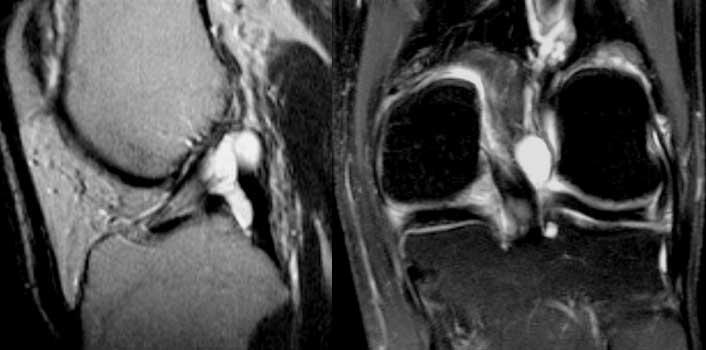

Lưu ý rằng trên ảnh mặt phẳng vành và mặt phẳng ngang, các bó sợi ACL nằm sát ngay bên cạnh xương của hõm liên lồi cầu (mũi tên).

Tuyệt đối không được có dịch giữa các bó sợi ACL và xương lồi cầu ngoài (gọi là ‘dấu hiệu hõm rỗng’).

TRÁI: Đứt ACL cấp tính. Các bó sợi ACL quá nằm ngang so với trần liên lồi cầu. PHẢI: Gián đoạn các bó sợi.

Ca bệnh bên trái cho thấy dây chằng có hướng quá nằm ngang và các bó sợi bị gián đoạn, tức là có hướng bất thường và mất liên tục.

TRÁI: Các bó sợi ACL có hướng bình thường nhưng không bám vào lồi cầu đùi. PHẢI: Dấu hiệu hõm rỗng: dịch áp sát mặt trong lồi cầu ngoài.

Đôi khi dễ đánh giá hơn liệu các bó sợi có còn bám vào xương hay không khi quan sát trên mặt phẳng vành.

Tuyệt đối không được có dịch áp sát mặt trong lồi cầu ngoài.

Nếu có dịch ở vị trí này, được gọi là ‘dấu hiệu hõm rỗng’, cho thấy ACL đã bị bong khỏi điểm bám trên lồi cầu đùi.